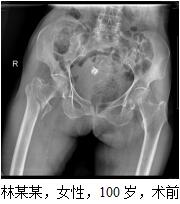

患者林某某,女性,100岁,秀屿区东峤镇人,于2016-08-30在家摔倒,右髋部疼痛伴活动受限,不能站立及行走。于2016-08-31求诊我院,急诊拟“右股骨转子间骨折”收住我院。患者既往有高血压病、心脏病、慢支、肺气肿等病史。患者入院后,医院领导高度重视,组织心血管内科、呼吸内科、麻醉科等相关科室全院大会诊,并制定详细周密的诊疗计划,决定予以行薇创骨折内固定术。完善相关术前准备后,于2016-09-02在麻醉下行右股骨转子间骨折闭合复位PFNA内固定手术治疗。手术时间才50分钟左右,手术过程顺利,术中出血少。术后di1天,患者右髋部疼痛已缓解明显,可以自行床上翻身、坐起来,术后12天,患者康覆出院,成效满意。